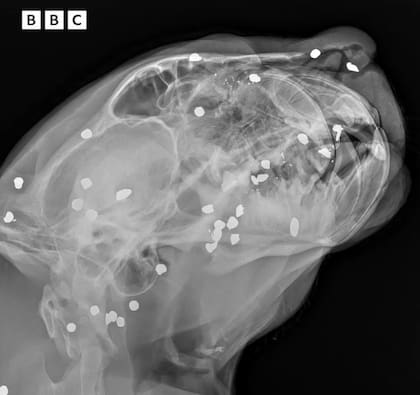

El felino, con su pelaje moteado característico, se aferró con sus patas a una lona de rescate y fue sacado del agua rápidamente por los miembros del equipo. Posteriormente, en una clínica de Manaos, se confirmó la magnitud de sus lesiones. Un examen exhaustivo que incluyó radiografías fechadas el 1 de enero de 2021, mostró que el jaguar había recibido un disparo de escopeta en la cabeza. Las imágenes revelaron la presencia de más de 30 fragmentos de plomo incrustados en su cuello, cara y cráneo. Además, el ataque le provocó la rotura de varios dientes, complicando aún más su estado.

Joana Darc, secretaria de Protección Animal de Manaos, expresó su consternación ante la situación. “Nos asustamos mucho al ver que había sido alcanzada por varios disparos de escopeta, con esos proyectiles de plomo”, declaró Darc en un video que dio a conocer la BBC en sus redes sociales. “Fue entonces cuando vimos que tenía más de 30 proyectiles en todo el cuerpo, pero la mayoría estaban concentrados en la cabeza, en el cráneo”, agregó. La gravedad de las heridas evidenció la intencionalidad del ataque contra el animal.